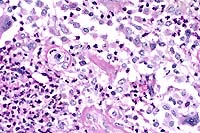

The colon contains large, focally extensive to confluent areas of mucosal ulceration which are covered by a layer of fibrinopurulent material with hemorrhage. The remaining lamina propria is increased in cellularity due to mononuclear cells with occasional neutrophils. Crypts are dilated and filled with degenerative inflammatory and epithelial cells. Re-epithelialization is occurring along the luminal surface of the mucosa in some areas. The submucosa is markedly edematous with dilated lymphatics, and scattered inflammatory cells. The tunica serosa is also edematous and mildly to moderately infiltrated with mononuclear cells. There are focal hemorrhages on the serosal surface and mesothelial cells are hypertrophic.

Case 3-1. Colon. Demonstrates erosive colitis with lymphoid depletion, herniation of crypt glands into the submucosa, and intraluminal fibrinosuppurative exudate. 20x

AFIP Diagnosis: Colon: Colitis, erosive, suppurative, subacute, diffuse, severe, with lymphoid depletion, abundant intraluminal suppurative exudate and numerous bacilli, Rhesus monkey (Macaca mulatta), primate.